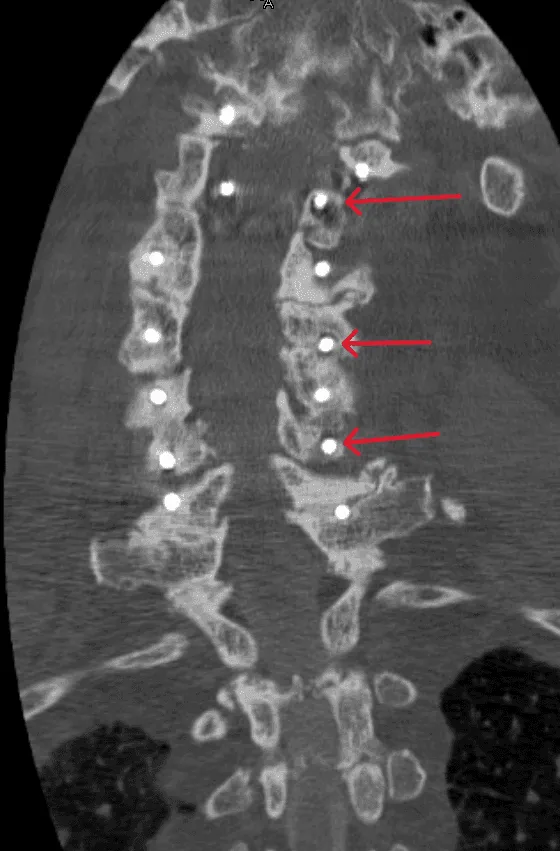

CT scan showing a spine with highlighted vertebrae indicated by red arrows.

Hardware Failure

Implant migration, separation, or mechanical failure requiring revision surgery.